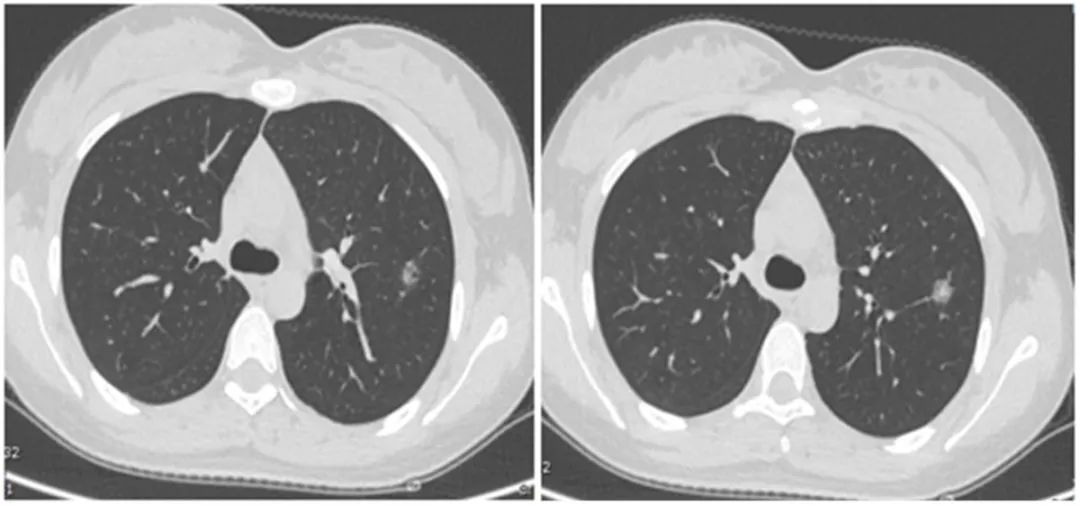

没想到我这么大岁数,切掉一个肺叶的十年后,再次做这么复杂的手术还这么顺利。 D大爷今年72岁,10年前曾行左肺上叶切除+淋巴结清扫术,手术标本病理为腺癌,术后给予了四次化疗。当时的胸部CT即可见右肺上叶小结节影,术后定期复查,病灶缓慢增大,一度略有缩小,此后再次逐渐增大。结合患者一直随访的影像学资料,杨如松院长考虑为右上肺新发恶性肿瘤。 2015年胸部CT 2020年胸部CT 虽然患者及其家属手术的意愿非常强烈,但此手术难度较高,原因在于: 1.患者年龄较高,手术风险大。 2.患者10 年前肺癌手术切除左边肺的一半,肺功能丧失较多。 3.病灶在右上肺的深部,切除有一定的难度。 为了保证患者术后的生活质量,我们不能够做肺的楔形切除这样的简单肺手术,而需要行肺段的切除。 EDDA重建提示病灶位置深 如果放在以前该患者就只能做做放化疗等保守治疗了。幸亏南京胸科医院目前引进了各种国内乃至国际上的先进技术。 如EDDA术前三D成像技术;只有单一3cm长切口的单孔胸腔镜技术;近红外荧光镜肺段、亚肺段精准定位技术等。 有了这些技术,杨如松院长心中有了底气。杨院长根据病人的情况设计手术方案,尽量减轻手术创伤,让接受第二次肺部复杂手术的高龄病人能够耐受,并且在术后能够顺利恢复。 根据术前EDDA三维重建,患者进行了单孔荧光胸腔镜S1a+2a切除术,术中先用ICG反染法确定段间面,再用膨胀萎陷法印证段间面,这保证了手术切除的精准性。 患者术中快速病理为贴壁型腺癌,这也印证了杨如松院长术前对患者肺结节良恶性的判断。 术后5天,D大爷非常顺利的出院了。出院前开心的窦大爷连声感谢杨如松院长:没想到我这么大岁数,切掉一个肺叶的十年后,再次做这么复杂的手术还这么顺利,谢谢、谢谢! 基本情况